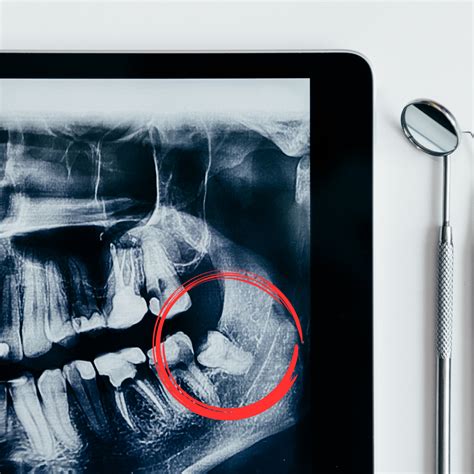

- Muelas del juicio: Si las muelas del juicio no tienen espacio, ejercerán presión y pueden descolocar piezas adyacentes.

Muelas del Juicio

Las muelas del juicio son los terceros molares, los cuatro dientes adultos permanentes ubicados en la parte posterior de la boca, en las mandíbulas superior e inferior. Suelen brotar entre los 17 y los 21 años. A veces, las cuatro muelas del juicio salen normalmente y no causan ningún problema, sin embargo, a menudo crecen en ángulo o quedan total o parcialmente atrapadas (impactadas) en la mandíbula o debajo del tejido de las encías, lo que puede causar problemas.

¿Cuándo es necesaria la extracción de las muelas del juicio?

Su dentista puede recomendarle quitar sus muelas del juicio si usted:

- Tiene dolor dental cerca de la parte posterior de la boca.

- Atrapa comida y desechos alrededor de sus muelas del juicio.

- Desarrolla la enfermedad de las encías, particularmente alrededor de los molares.

- Tiene caries en una muela del juicio parcialmente erupcionada.

- Desarrolla un quiste alrededor de una o más muelas del juicio.

- Tiene daño en los dientes cercanos o en el hueso circundante.

En muchos casos, los dentistas recomiendan la extracción de las muelas del juicio como medida preventiva, incluso si no tiene ningún síntoma. La extracción se puede hacer a cualquier edad, pero muchos dentistas recomiendan su extracción al final de la adolescencia o al comienzo de los 20 años. Durante esta etapa de desarrollo, las muelas del juicio aún se están formando.